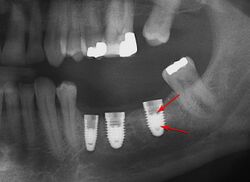

Fracture of abutment screws in three consecutive implants due to severe over-torqueing.

In a three-piece implant the abutment is fixed on the implant with a screw butt joint.[4] This screw needs to be tightened to a predetermined torque with a dental torque wrench, in order to avoid screw loosening during chewing, which can often create a counter-clockwise torque on the implant-abutment interface, encouraging the abutment screw to come loose. This can largely be prevented with proper screw design and torquing of the abutment.